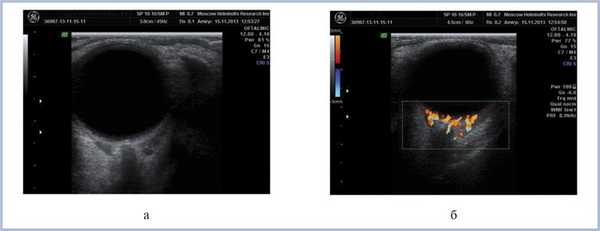

В настоящее время, спустя 6 мес после постановки диагноза и проведения 4 курсов ПХТ, состояние больного удовлетворительное. Патологических изменений со стороны ЦНС и других систем органов на данный момент не выявлено. Зрение обоих глаз с миопической коррекцией 1,0. Клинически отмечается положительная динамика в виде уплощения и уменьшения площади поражения (рис. 7, 8). Аналогичные результаты демонстрируют и инструментальные методы исследования (рис. 9). Однако в связи с наличием остаточного опухолевого процесса больной был направлен к гематологам для продолжения курса лечения (ПХТ).

Рис. 9. Дуплексное сканирование левого глаза и орбиты через 6 мес после ПХТ. Определяется уменьшение размеров опухолевой ткани в В-режиме (а), сохранность собственной васкуляризации в режиме ЦДК (б).